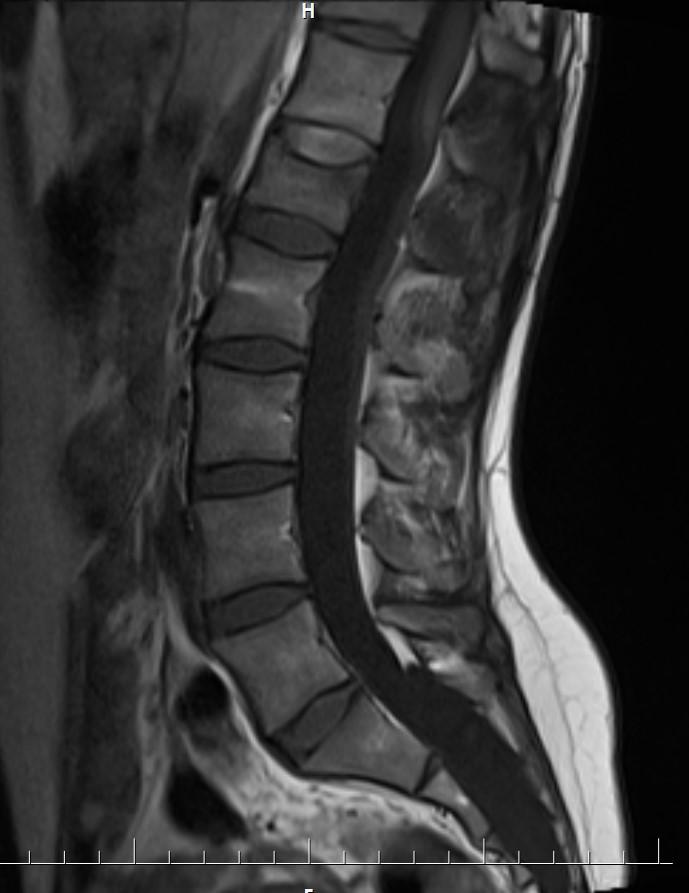

Answer: Occult intrasacralmeningocele

MR images demonstrated large cystic lesion in the sacral canal.

Occult intrasacralmeningoceletypically appear hypodenselesion (isodense to CSF) enlarging the sacral thecal sac which may displace the nerve roots.

MRI is the best modality to assess an occult intrasacralmeningocele.

• T1: hypointense(isointense to CSF)

• T2: hyperintense (isointense to CSF)